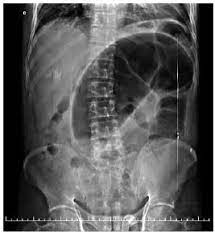

Para mais, em caso de suspeita de abdome agudo obstrutivo solicita-se um raio-X de abdome em pé e deitado e um raio-X de tórax em pé. Esse último visa identificar possível pneumoperitônio (sinal do crescente), decorrente de ruptura de alças, que indica necessidade de abordagem cirúrgica imediata.

Para além desse achado, também é possível evidenciar no raio-X de abdome do paciente com abdome agudo obstrutivo a presença de nível hidroaéreo e aumento da espessura das alças com presença de haustrações. E ainda, na presença de uma obstrução total, haverá ausência de gás nos cólons e no reto.

Por fim, no paciente com volvo de sigmóide, é possível observar o sinal do “U invertido”, também conhecido como sinal do “grão de café”. E mais, apesar do uso do contraste não ser realizado de rotina no raio-X do paciente com obstrução intestinal, na presença de volvo sigmóide, pode ser possível observar o sinal do “bico de pássaro”.

Para mais, caso o raio-X não evidencie achados que indiquem intervenção cirúrgica imediata, recomenda-se a realização de uma tomografia computadorizada (TC) de abdome, a fim de avaliar o local em que está ocorrendo a obstrução. São achados que devem elevar as suspeitas de obstrução quando houver presença de nível hidroaéreo e dilatação das vísceras.